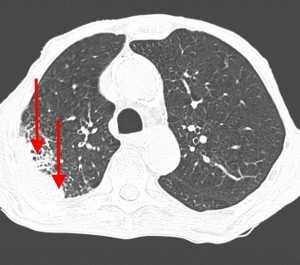

Гематогенные метастазы наиболее часто локализуются в периферических отделах легких, вдали от крупных сосудисто-бронхиальных пучков, вблизи плевральной оболочки. При множественных поражениях гематогенного характера наблюдается тенденция к увеличению количества очагов в направлении «сверху-вниз». Чаще гематогенные метастазы расположены хаотично, вне четкой связи с бронхами и видимыми легочными сосудами. Практически не бывает такого, чтобы гематогенные вторичные узлы находились только с одной стороны, или занимали только одну долю или сегмент. При наличии такого распределения в первую очередь нужно думать о туберкулезе (верхние доли), множественных абсцессах и т. д.

Гематогенные метастазы саркомы мягких тканей бедра на КТ (справа) и рентгенограмме (слева).